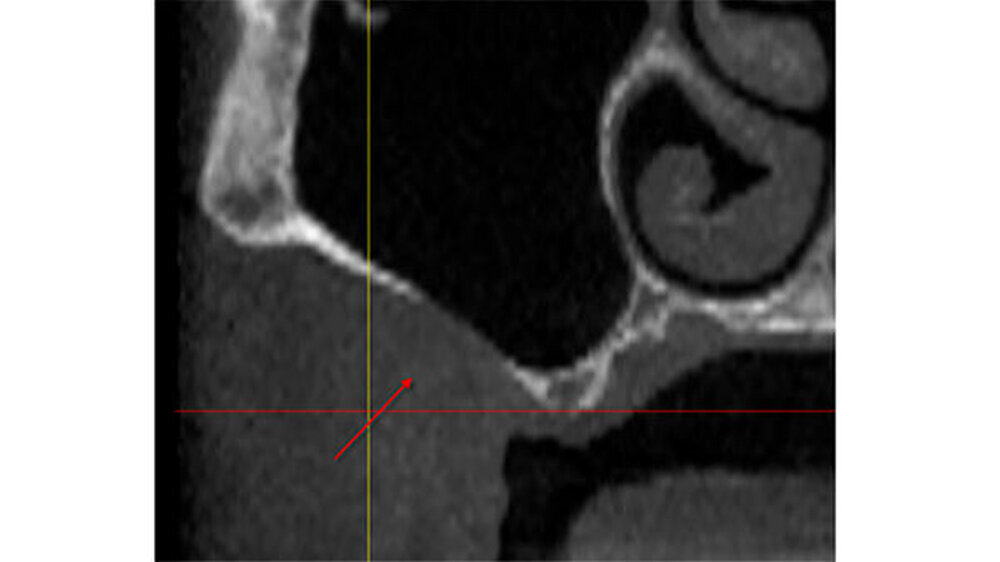

Die vor der geplanten Implantation gesichtete DVT hatte zunächst keinen knöchernen Defekt ausgewiesen. Erst bei nochmaligem und kompletten "Durchscrollen" aller Aufnahmen wurde der Defekt sichtbar (Abbildungen 2 bis 5).